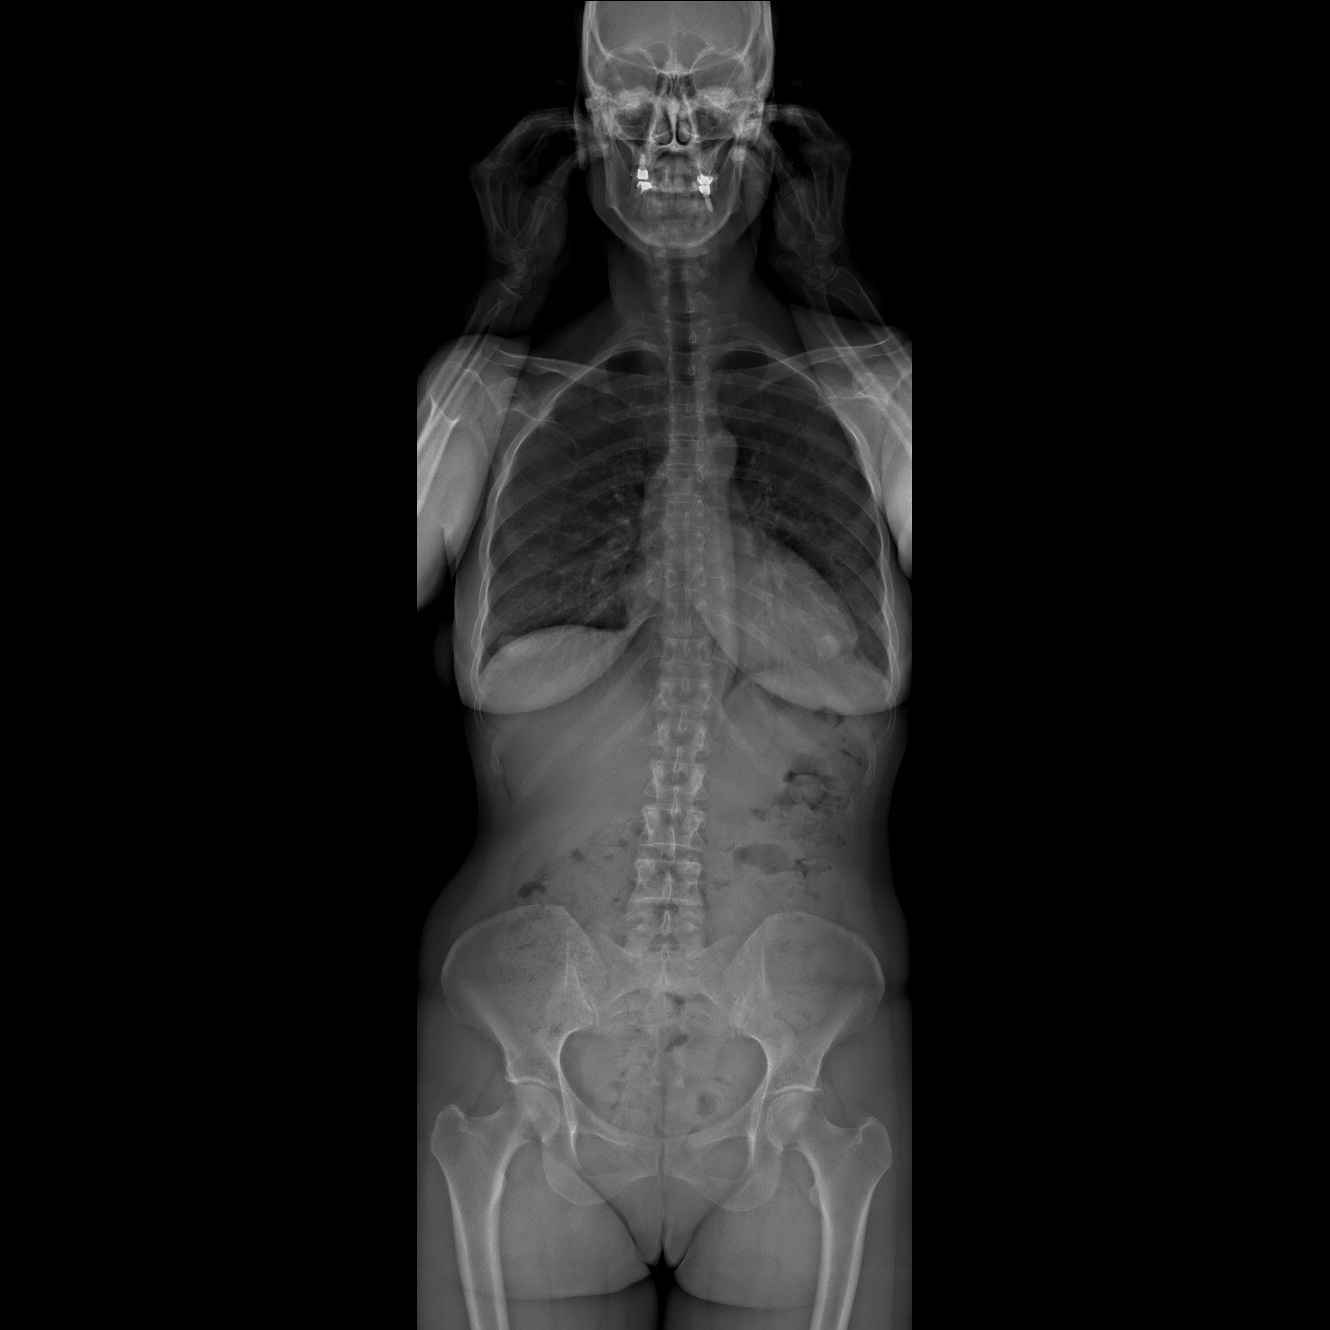

Un examen corps entier, debout, en 2D et en 3D

EOS permet pour la première fois :

• la visualisation du corps entier en position debout ;

• des images de face et de profil ;

• une reconstruction en trois dimensions, utile dans de nombreuses pathologies de la statique du corps.

L’EOS est devenu la méthode de référence pour :

• le diagnostic et le suivi des scolioses et anomalies du rachis ;

• l’analyse de la statique globale du corps, notamment chez les adultes ;

• le pangonogramme des membres inférieurs (longueurs, axes, déviation) ;

• l’évaluation de la statique pelvienne.